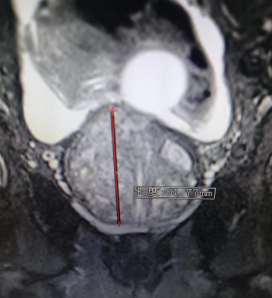

每当夜深人静的时候 您是否有尿频、尿急、夜尿多 总是在如厕或正在如厕的路上 “男”言之隐 痛苦不堪 …… 近日,94岁高龄的刘老爷子在孙子的陪同下来到贵州航天医院泌尿外科,因为排尿困难10余年,存在尿等待、尿无力、尿线细弱、尿不尽等问题,夜尿约7-8次,1月前出现无法排尿,反复留置导尿管,痛苦不堪。 因患者72岁儿子患有前列腺增生症,不久前在我院泌尿外科进行了前列腺钬激光剜除手术,对治疗效果较为满意,术后3天拔除尿管正常排尿出院,所以家人就抱着试一试的态度来到航天医院泌尿外科咨询。 泌尿外科根据患者病情及辅助检查,结合尿动力学检查排除神经源性膀胱,诊断为:前列腺增生症。 术前磁共振提示前列腺重度增生 泌尿外科团队为该患者制定了“经尿道前列腺钬激光剜除术”治疗方案。手术过程顺利。 经尿道前列腺钬激光剜除术手术中 激光剜除前列腺 粉碎前列腺组织 术后3天拔除导尿管,拔管后患者排尿较为顺畅,解决了困扰刘老爷子十余年的“男”题,极大提高了生活质量! 术前 术后 前列腺钬激光剜除术 (HoLEP)及前列腺增生科普 什么是前列腺增生 良性前列腺增生,也称为前列腺肥大症,是一种男性常见的疾病,其主要表现为前列腺组织的异常增生。这种增生主要发生在前列腺的尿道周围,使得尿道变窄,从而引起一系列的问题。大约50%的50岁以上的男性都会出现前列腺增生的症状。在大多数情况下,前列腺增生是一个自然的衰老过程,不会对健康构成威胁。但是,如果增生的前列腺组织阻塞了尿道,可能会引发一系列的问题。 前列腺增生症状 *尿频:尤其是夜间尿频。 *尿急:甚至可能会出现尿失禁。 *尿流变弱,尿不尽。 *血尿:前列腺黏膜上毛细血管充血及小血管扩张,并受到膀胱充盈、收缩的牵拉而破裂出血。 *尿路感染:尿流梗阻是引起感染的先决条件,故前列腺增生压迫易发生膀胱颈、后尿道及膀胱炎症。 *尿潴留:膀胱结石、肾积水和肾功能不全。 *可能出现便秘、腹胀等肠道问题。 经尿道前列腺钬激光剜除术 (HoLEP) 1.经尿道前列腺钬激光剜除术(HoLEP)是目前治疗前列腺增生最先进的手术方式之一,其原理与传统电切术完全不同。 2.完整的剜除手术包括增生腺体的剜除和组织粉碎吸出两个过程。 3.术中医生利用光纤传导激光,将增生的腺体切除,再以组织粉碎器将腺体组织切成碎块吸出体外,恢复尿道通畅。 前列腺增生什么情况下需要手术 1.下尿路症状严重并明显影响生活质量者。 2.前列腺增生导致反复尿潴留患者(至少在一次拔管后不能排尿或两次尿潴留)。 3.前列腺增生导致反复血尿,药物治疗无效者。 4.前列腺增生导致反复泌尿系感染者。 5.前列腺增生合并膀胱结石者。 6.前列腺增生导致继发性上尿路积水(肾积水)者。 前列腺钬激光剜除术比较 传统的前列腺电切术的优势 1.钬激光对水的吸收率极高,钬激光能在充满水的尿道和膀胱内有效照射,不会损伤其它组织。 2.剜除层面清晰,剜除腺体彻底,不易复发。 3.止血彻底,二次出血风险低。 4.术后恢复快,半天即可活动及饮食,最快术后24小时可拔除尿管。 5.术后控尿功能好,保留性功能,时间短、安全性高。 传统前列腺电切术后 前列腺钬激光剜除术后 “经尿道前列腺钬激光剜除术(HoLEP)”已逐渐成为前列腺增生治疗的“金标准”。 贵州航天医院泌尿外科于2017年率先在遵义市开展经尿道前列腺钬激光剜除术,每年手术量300余台,该技术的开展,将前列腺增生手术治疗水平提高到了一个新高度,让更多病人得到更好的治疗,尤其是高龄、高风险的患者,使其摆脱尿管,恢复正常的生活和工作,为他们带来了福音,解决了他们的“男”言之隐! 贵州航天医院泌尿外科 前列腺、盆底疾病及尿控专家团队 石 英 泌尿外科主 任 学科带头人 主任医师 中国医师协会泌尿外科分会感染协作组委员,奥林巴斯泌尿系软镜西南区专家组成员,西南地区第一批输尿管软镜专家组成员,贵州省医学会泌尿外科分会委员,贵州省性学会理事,贵州省性学会常务委员,贵州省泌尿外科专业医疗质量控制中心专家委员会委员。 从事泌尿外科专业近30年,熟练掌握泌尿系各类疾病的诊治,具有丰富的临床经验,擅长泌尿系结石、腹膜后肿瘤及泌尿系肿瘤的手术治疗,对泌尿系感染、泌尿系结核、尿源性脓毒血症的救治有独到的见解及抢救经验,在贵州省率先引入输尿管软镜技术,同时在男科领域,对男性阳痿、早泄及前列腺疾病有很深的研究。 李国成 泌 尿 外 科 副 主 任 医 师 中国人体健康科技促进会男科学专业委员会委员,贵州省性学会泌尿外科分会委员,贵州省医学会男科学分会委员,遵义市医学会男科学分会副主任委员兼秘书长,遵义市医学会泌尿外科分会常务委员,贵州航天医院男科带头人。 从事泌尿外科及男科工作10余年,曾多次在上海交通大学附属第一人民医院,中国中医科学院西苑医院进修学习男科;擅长性功能障碍的诊治,男性整形手术,前列腺增生激光手术,显微手术等。 娄 进 泌 尿 外 科 主 治 医 生 贵州省医学会男科学分会前列腺组委员、遵义市医学会男科学分会常委,于陆军军医大学第一附属医院(西南医院)进修学习,师从沈文浩教授。 擅长神经源性膀胱、膀胱过度活动症、间质性膀胱炎、压力性尿失禁等排尿功能障碍性疾病以及女性盆底器官脱垂、前列腺增生的微创治疗。 贵州航天医院泌尿外科简介 • ✦ 基本情况 ✦ • 贵州航天医院泌尿外科是贵州省临床重点专科,具备先进检查及治疗设施,可进行各种泌尿外科所需临床检查和治疗。拥有先进的美国科医人钬激光碎石及前列腺剜除系统、体外冲击波碎石机、等离子电切设备、奥林巴斯输尿管软镜、STORZ输尿管电子软镜、腹腔镜、膀胱镜、输尿管镜、肾镜、美国KLS能量平台及各种显示系统,男科专用的ED超声治疗仪、精液分析、显微镜、男科检查平台、尿动力仪、结石分析仪等。 除了传统的开放性手术外,已常规开展各种微创性手术,同时在尿动力学及结石成分方面的研究已走在省内前列,在贵州省内率先开展前列腺钬激光剜除术治疗前列腺增生症,等离子电切术在前列腺增生、膀胱肿瘤、在尿道狭窄中手术的应用,腹腔镜手术(肾囊肿、肾上腺肿瘤、肾输尿管结石及肾切除手术),肾癌、肾盂癌、输尿管癌、膀胱癌、前列腺癌根治术,泌尿系统畸形及泌尿系重建,在遵义地区率先开展钬激光技术应用于泌尿外科临床,率先使用输尿管硬镜、软镜及肾镜联合钬激光治疗泌尿系结石,开展尿动力学、泌尿系结石分析,填补了遵义地区空白,率先开展针状肾镜激光碎石取石术。 • ✦ 诊疗范围 ✦ • 泌尿系肿瘤、炎症、小儿泌尿系疾病、男科疾病、女性排尿异常与盆底功能障碍疾病。如:肾上腺肿瘤、肾肿瘤、肾盂输尿管肿瘤、膀胱肿瘤、前列腺肿瘤、生殖器肿瘤、排尿功能障碍、泌尿系畸形及肾后性肾功能障碍、女性尿道综合征、泌尿系感染以及泌尿道疼痛、婴幼儿男性性腺和性器官发育异常、青春期男性性器官和功能发育延迟、男性功能障碍包括、男性生殖功能障碍、男子节育与避孕、中老年男子生殖健康以及老年男子性腺功能减退症、生殖器官常见疾病、男性生殖器感染以及性传播疾病、外生殖器官畸形与矫形、损伤。 二、泌尿系结石。如:肾结石、输尿管结石、膀胱结石、前列腺尿道结石、泌尿系畸形合并结石、尿流改道术后合并泌尿系结石。 三、独立开展男科疾病的诊治,专注男性健康。 • ✦ 咨询信息 ✦ • 门 诊 地 址:门诊部010诊室 坐诊时间: 周一至周五(08:00-12:00;13:00-17:00) 周末及节假日(08:00-12:00;13:00-16:00) 咨询电话 门 诊:28690349 医生办公室:27677326 病房护士站:27677518 End